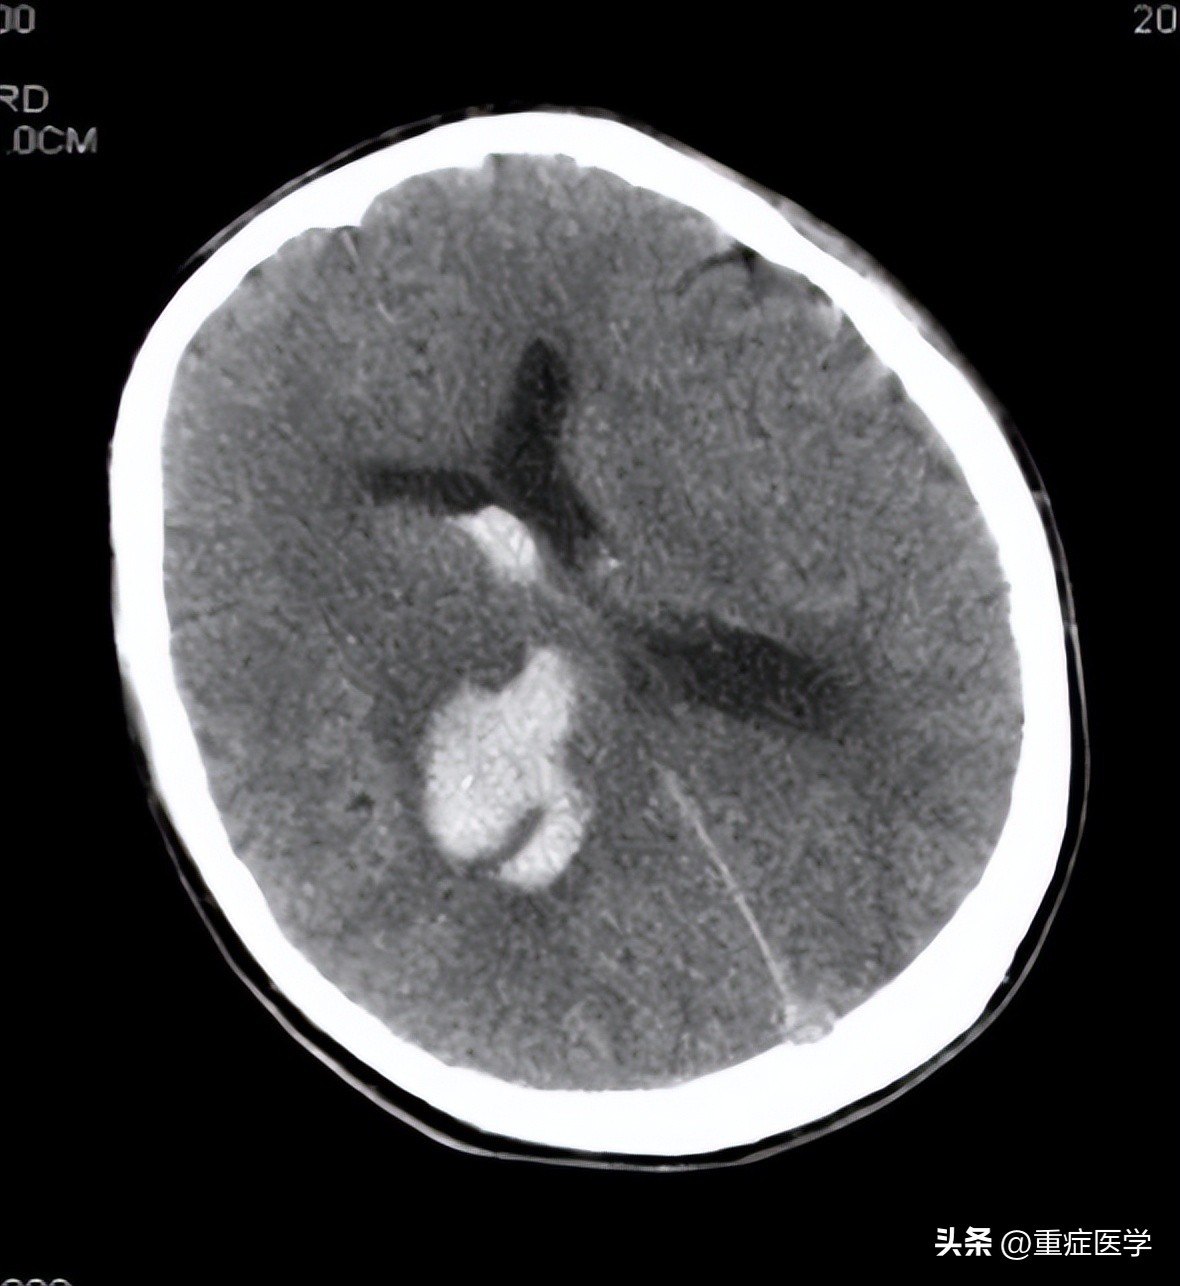

急诊就诊,当时测血压 200/100 mmHg,头颅 CT 示右侧基底节、丘脑出血,破入脑室。

图:患者头颅 CT 影像